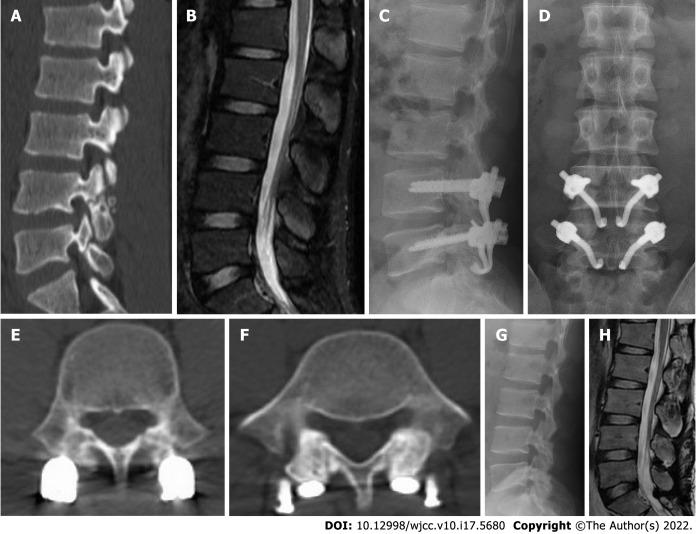

We designed a new anatomic hook-rod-pedicle screw system for young patients with lumbar spondylolysis. The isthmus and the corresponding pedicle screw entry point were exposed through the intermuscular approach. Autogenous iliac bone graft was obtained to bridge the isthmus defect, and then the anatomic hook-rod-pedicle screw system was used to fix the isthmus in 15 young patients.

At 24 mo follow-up, the visual analogue scale score of low back pain decreased from 6.73 ± 0.88 to 0.73 ± 0.59, and the Oswestry disability index score decreased from 58.20 ± 8.99 to 7.87 ± 4.97. Computed tomography showed bilateral isthmic bone healing in 14 cases and unilateral isthmic bone healing in 1 case. Magnetic resonance imaging showed that the lumbar disc signal of diseased segment and adjacent segments had no change compared with that before surgery. The pain visual analogue scale score of the donor site was 0.20 ± 0.41 at the last follow-up. According to the Modified Macnab score, the excellent and good rate was 100%.

方法

随访24个月时,腰痛视觉模拟评分从6.73±0.88降至0.73±0.59,Oswestry功能障碍指数评分从58.20±8.99降至7.87±4.97。CT显示14例双侧峡部骨愈合,1例单侧峡部骨愈合。MRI显示病变节段及相邻节段腰椎间盘信号与术前相比无变化。末次随访时供区疼痛视觉模拟评分为0.20±0.41。根据改良Macnab评分,优良率为100%。